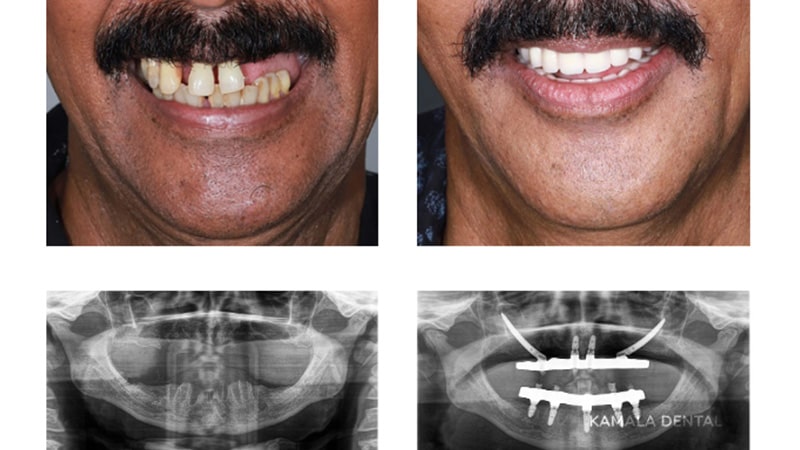

Zygomatic Implants

Zygomatic implants are used when there is little or no bone left in the upper jaw. Instead of relying on the weakened jawbone, the nearby zygomatic bone is used for support. With two straight implants in the front and two tilted long implants anchored in the zygomatic bone, they provide strong support for hybrid prostheses in cases of severe bone loss in the upper jaw.